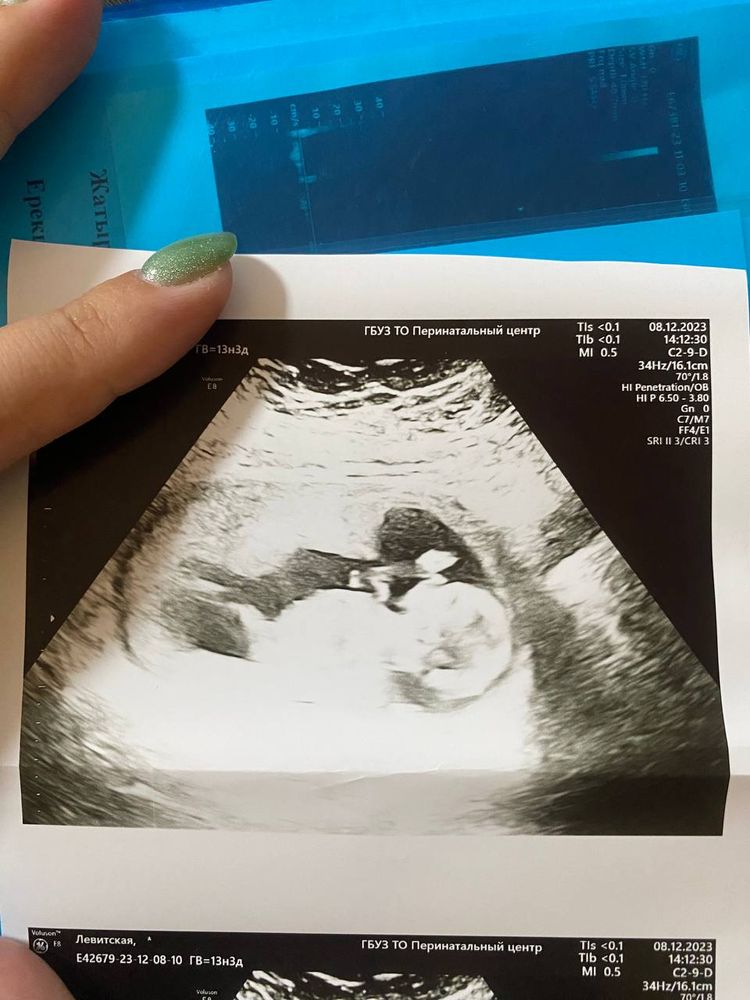

Ура! 1 скрининг и много не понятных слов. Вроде всё впорядке?

Аппарат узи, конечно, древний в перинатальном центре. Но вроде видно, что в животе ЧЕЛОВЕК.

Пол сказали, что лучше смотреть на втором скрининге, но кому-то говорили и на первом. Фото прикладываю, может есть любители, как я, гадать по фото!)))

Мне кажется, что девочка